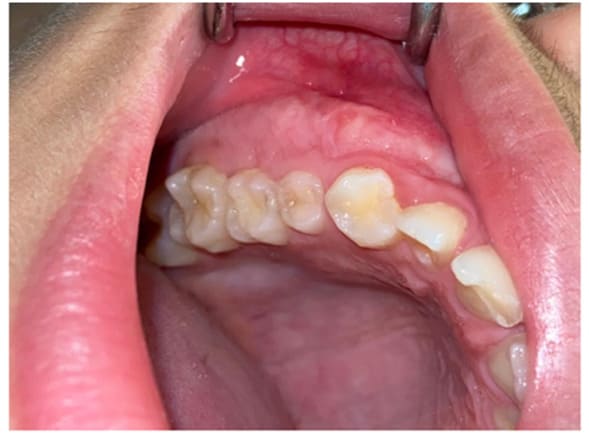

Case 1: a 12-year-old male patient from Catanzaro, Italy, was referred to the Odontostomatology Department of Galliera Hospital in Genoa, Italy. The patient presented an expansive mass involving the right upper jaw (Fig. 2) and retained right permanent upper canine. Upon clinical examination, the patient exhibited a hard lesion causing altered eruption of the dental element 1.3, a lack of space in the dental arch, subsequent to the exfoliation of the deciduous canine, and a buccal protuberance of the permanent canine, in close proximity to the lateral incisor root. Initial bidimensional radiographic examination (OPT) revealed a ground-glass opacity within the right maxillary sinus and malposition of the permanent canine. To delineate the lesion in three dimensions and to locate the right upper canine accurately, cone-beam computed tomography (CBC, Fig. 1) was necessary. The CBCT depicted the buccal position of the canine and defined the borders of the fibro- osseous lesion, which also involved the buccal aspect of the posterior elements, leading to altered passive eruption.

In Case 1, under local anesthesia (2% Mepivacaine Hydrochloride with 1:100000 adrenaline), a mucoperiosteal flap was raised (Fig. 3), fully exposing the fibro-osseous tissue. An incisional biopsy was then performed (Fig. 4), obtaining a sample measuring 2 cm x 0.6 cm x 0.3 cm (Fig. 5).

Figure2: Pre-operative situation

Figure3: Elevation of the flap and exposition of the lesion.